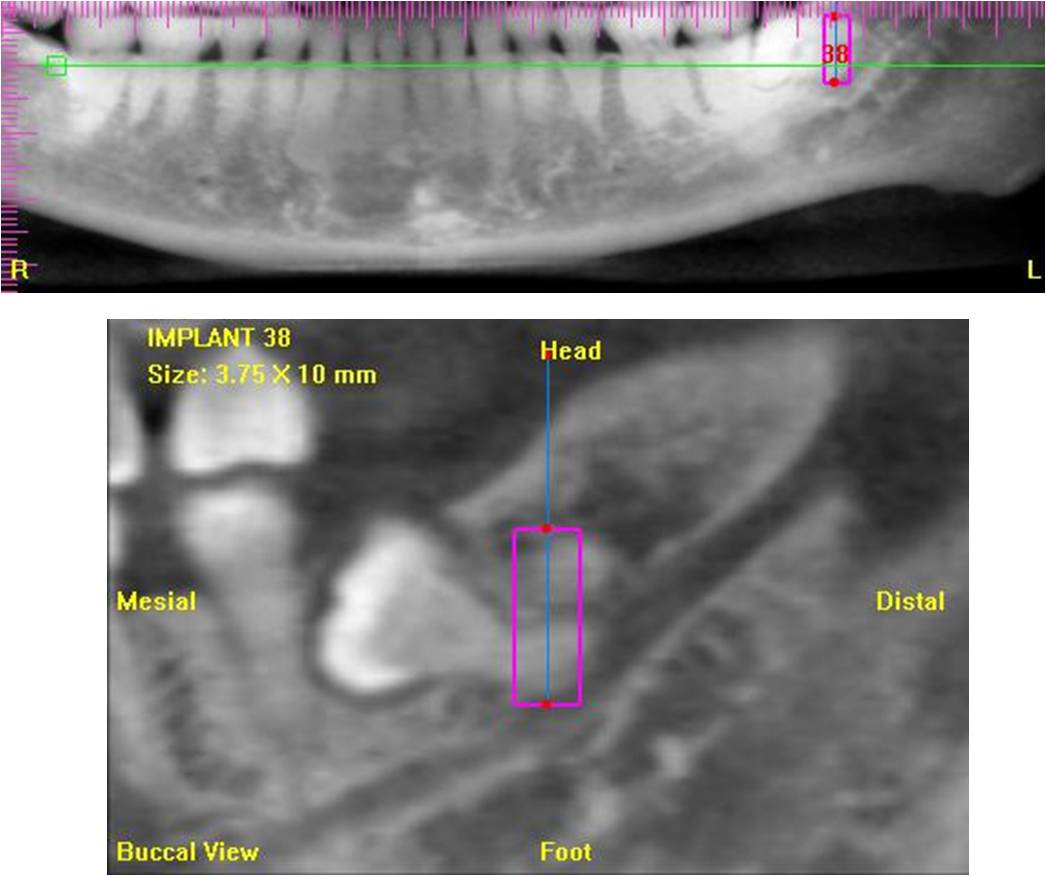

左下阻生齒:電腦斷層評估,根尖處在下齒槽正上方